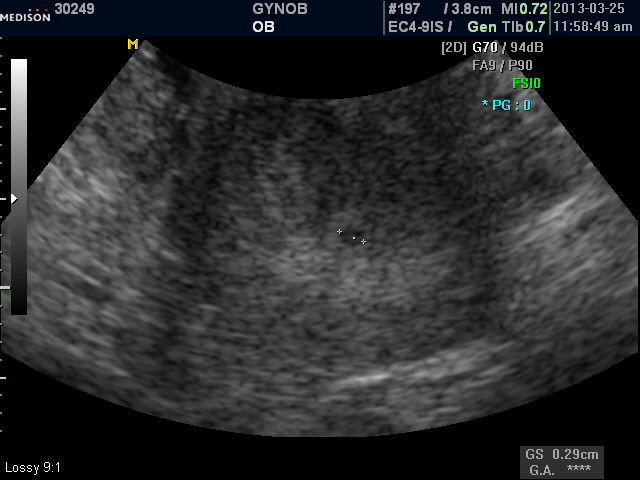

오늘 초음파를 보셨는데 두개의 아기집이 자리잡고 있네요..두 아기집 다 심장소리가 들려서 너무 벅찼어요.. 엄마는 아직 쌍둥이가  실감나지 않으신가 봐요..  건강하게 두 아기 다 잘 컸으면 좋겠어요~~^^